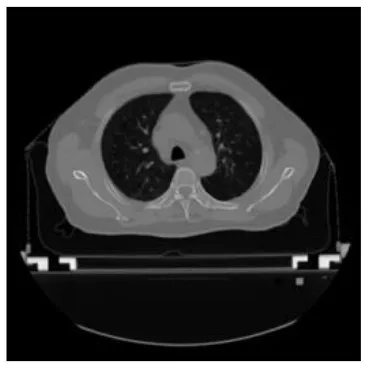

According to the acquired model parameters mentioned above, the testing set was calculated and examined. The performance of the modified algorithm for automatic organ segmentation in CT images is shown in Table 1. The organ contours segmented automatically by the algorithm were similar to those delineated by physicians manually. The model parameters including DSC, Accuracy, Recall, and Precision evaluation ones were served to evaluate the segmentation effectiveness of each organ in the validation and testing sets. In our work, the BCDU-Net CNN algorithm model was used to automatically segment different organs with the different training parameters such as epoch learning rate. The CT images which were randomly selected from the patients were put into the network model for training, and then the contours of different organs which were delineated automatically by the AI technology and manually by medical doctors were evaluated with the similarity coefficients, respectively. The results are given in Table 2. Most of the DSC values were better than 0.85 and among them the best even reached up to 0.9676. Generally, the automatic segmentation results met the requirements of clinical practice.

| Input CT image | Organs with manual segmentation | Organ with automatic segmentation | |

| Bladder | ![]() | ![]() | ![]() |

| Brainstem | ![]() | ![]() | ![]() |

| Eye-L | ![]() | ![]() | ![]() |

| Eye-R | ![]() | ![]() | ![]() |

| Femur-L | ![]() | ![]() | ![]() |

| Femur-R | ![]() | ![]() | ![]() |

| Heart | ![]() | ![]() | ![]() |

| Intestine | ![]() | ![]() | ![]() |

| Kidney-L | ![]() | ![]() | ![]() |

| Kidney-R | ![]() | ![]() | ![]() |

| Liver | ![]() | ![]() | ![]() |

| Lung-L | ![]() | ![]() | ![]() |

| Lung-R | ![]() | ![]() | ![]() |

| Mandible | ![]() | ![]() | ![]() |

| Rectum | ![]() | ![]() | ![]() |

| Spleen | ![]() | ![]() | ![]() |

| Stomach | ![]() | ![]() | ![]() |

The result of manual and automatic organ segmentation.